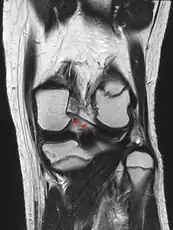

The Posterior meniscofemoral ligament (also known as the ligament of Wrisberg) is a small fibrous band of the knee joint. It attaches to the posterior area of the lateral meniscus and crosses superiorly and medially behind the posterior cruciate ligament to attach to the medial condyle of the femur.[1]

The posterior meniscofemoral ligament is found in 64.4% of the subjects in MRI scan of the knee.[1]